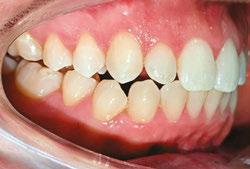

Clear Aligner Therapy (Figures 7, 8, 9)

Our orthodontic goals were the following:

1. Expand upper arch, correct crossbite

2. Close anterior open bite

3. Correct crowding

Patient J was prescribed a series of 43 aligners, with each aligner being worn for 20 hours a day for 1 week.

This comprehensive approach combining aligner therapy and MFT aimed to correct oral dysfunction, enhance breathing patterns, and ensure the long-term stability of orthodontic treatment. It combined clear aligners with MFT to address both the esthetic and functional aspects of the patient’s oral health.

Patient J wore her aligners for 20 hours a day, using the lingual edge of the aligners as a guide for her tongue position. However, when it came to her exercises, she found it challenging to adhere strictly to her routine. Due to this difficulty, I observed that even though progress was made in improving her swallowing pattern without requiring her to forcefully push her tongue through her teeth on the left side, she still pushed it on the right side. To address her open bite on the right side, I introduced elastics (Figures 10, 11) in addition to clear aligner therapy. During each MFT session, I asked the patient to grade the percentage of time she achieved Breathing Through the Nose (BTN), Tongue on a Spot (TOS), and Lips Together (LT).

Treatment results

Upon completion of MFT and active treatment phase with clear aligners (Figures 12, 13, 14, 15, 16), the patient revealed that snoring significantly reduced, her partner does not complain anymore, and she is breathing through the nose 75% of the time. The patient is holding her lips together 75% of the time and is able to keep her tongue on the spot 50% of the time.

Figures 13 and 14: 13. Right side upon the completion of active treatment. 14. Left side upon the completion of active treatment

Figures 15 and

15. Occlusal view upon the completion of active treatment. 16. Lower occlusal view upon the completion of active treatment